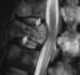

Metastasis to spine

Bone metastases, or osseous metastatic disease, is a category of cancer metastases that results from primary tumor invasion to bone. Bone-originating primary tumors such as osteosarcoma, chondrosarcoma, and Ewing's sarcoma are rare. [Source: Wikipedia ]